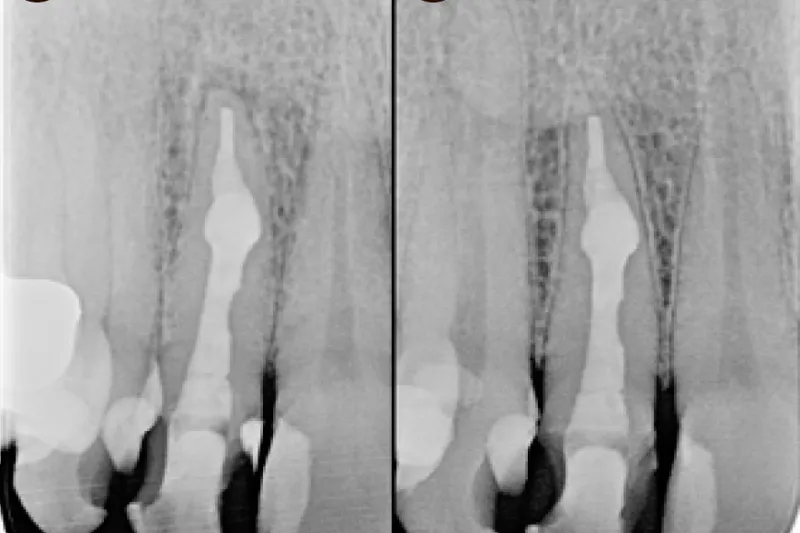

56-årig kvinde, henvist for rodbehandling af 2+, diagnosticeres efter CBCT pulpalt med necrosis pulpae et resorptio radicis dentis interna samt parodontitis apicalis 2+. Den interne rodresorption var uden perforation til rodoverfladen og lokaliseret i den nederste tredjedel af roden. Under operationsmikroskop blev der gennemført en kanalbehandling af +2 med udfyldning af resorptionskavitet. Der blev udrenset med roterende, manuelle og reciprokerende nikkel-titanium-instrumenter. Der blev foretaget aktiv skylning med bl.a. natriumhypoklorit. Rodfyldningen udførtes med en varm vertikal teknik med indledende applicering af tilpasset masterpoint apikalt for resorptionen. Efter syv måneder viste kontrolrøntgen heling af den apikale radiolucente zone.

56 year old female was referred for endodontic treatment of 12. The CBCT confirmed an internal root resorption in the apical third of the root canal, without perforation to the root surface. The tooth was non-vital and diagnosed with apical periodontitis. Using a microscope the root canal treatment was completed and the resorption cavity was filled. The root canal was prepared with rotating, manual and reciprocating NiTi instruments. Active irrigation was performed with sodium hypochlorite. The obturation procedure was a combination of warm vertical technique with initial application of a master cone placed apically to the resorption. Seven months later, the control x-ray showed healing of the apical radiolucent zone.